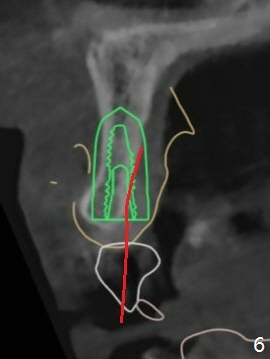

The patient has gummy smile (Fig.1).  The edentulous ridge at #10 has buccal concavity (Fig.2 *).  The surgical guide fits well without #9 distal trimming.  With 34 mg Xylocaine and 17 mcg Epinephrine infiltration at #10 and 12, the patient feels pain when 2.2 (in fact 1.9) x8.5 mm drill is being used.  When Septocaine is added, the osteotomy at #10 is found distal.  Out of curiosity, PA is taken with 2.2x10 mm drill in place; its trajectory seems satisfactory (Fig.3).  When a 2.5x13 mm 1-piece implant is placed free hand, it deviates palatal, which is confirmed with incision after addition of 34 mg Xylocaine and 34 mcg Epinephrine.  A new osteotomy is created by S-Mini Kit buccal to the previous one.  With Lindamann bur to adjust the position of the new osteotomy twice, the last drill (2.0 mm) apparently starts to perforate the apical portion of the buccal plate.  The perforation seems to enlarge when the mini implant is re-placed (Fig.4, 8 (green area) <30 Ncm).  With Vanilla graft (Fig.8 pink circles) and abutment height adjustment (Fig.4), a provisional is fabricated with occlusal clearance.  There are two reasons for failure of the surgical guide: failure to trim the tooth #9 distal (minor palatal guide displacement, Fig.5) and deflection of pointed drill and 2.2 mm drills over the hard palatal plate slope (Fig.6).  To avoid this complication, the pointed drill should be done free hand initially, after incision and obliquely (Fig.7).  The guide is placed to finish the rest of osteotomy if deem to be appropriate.